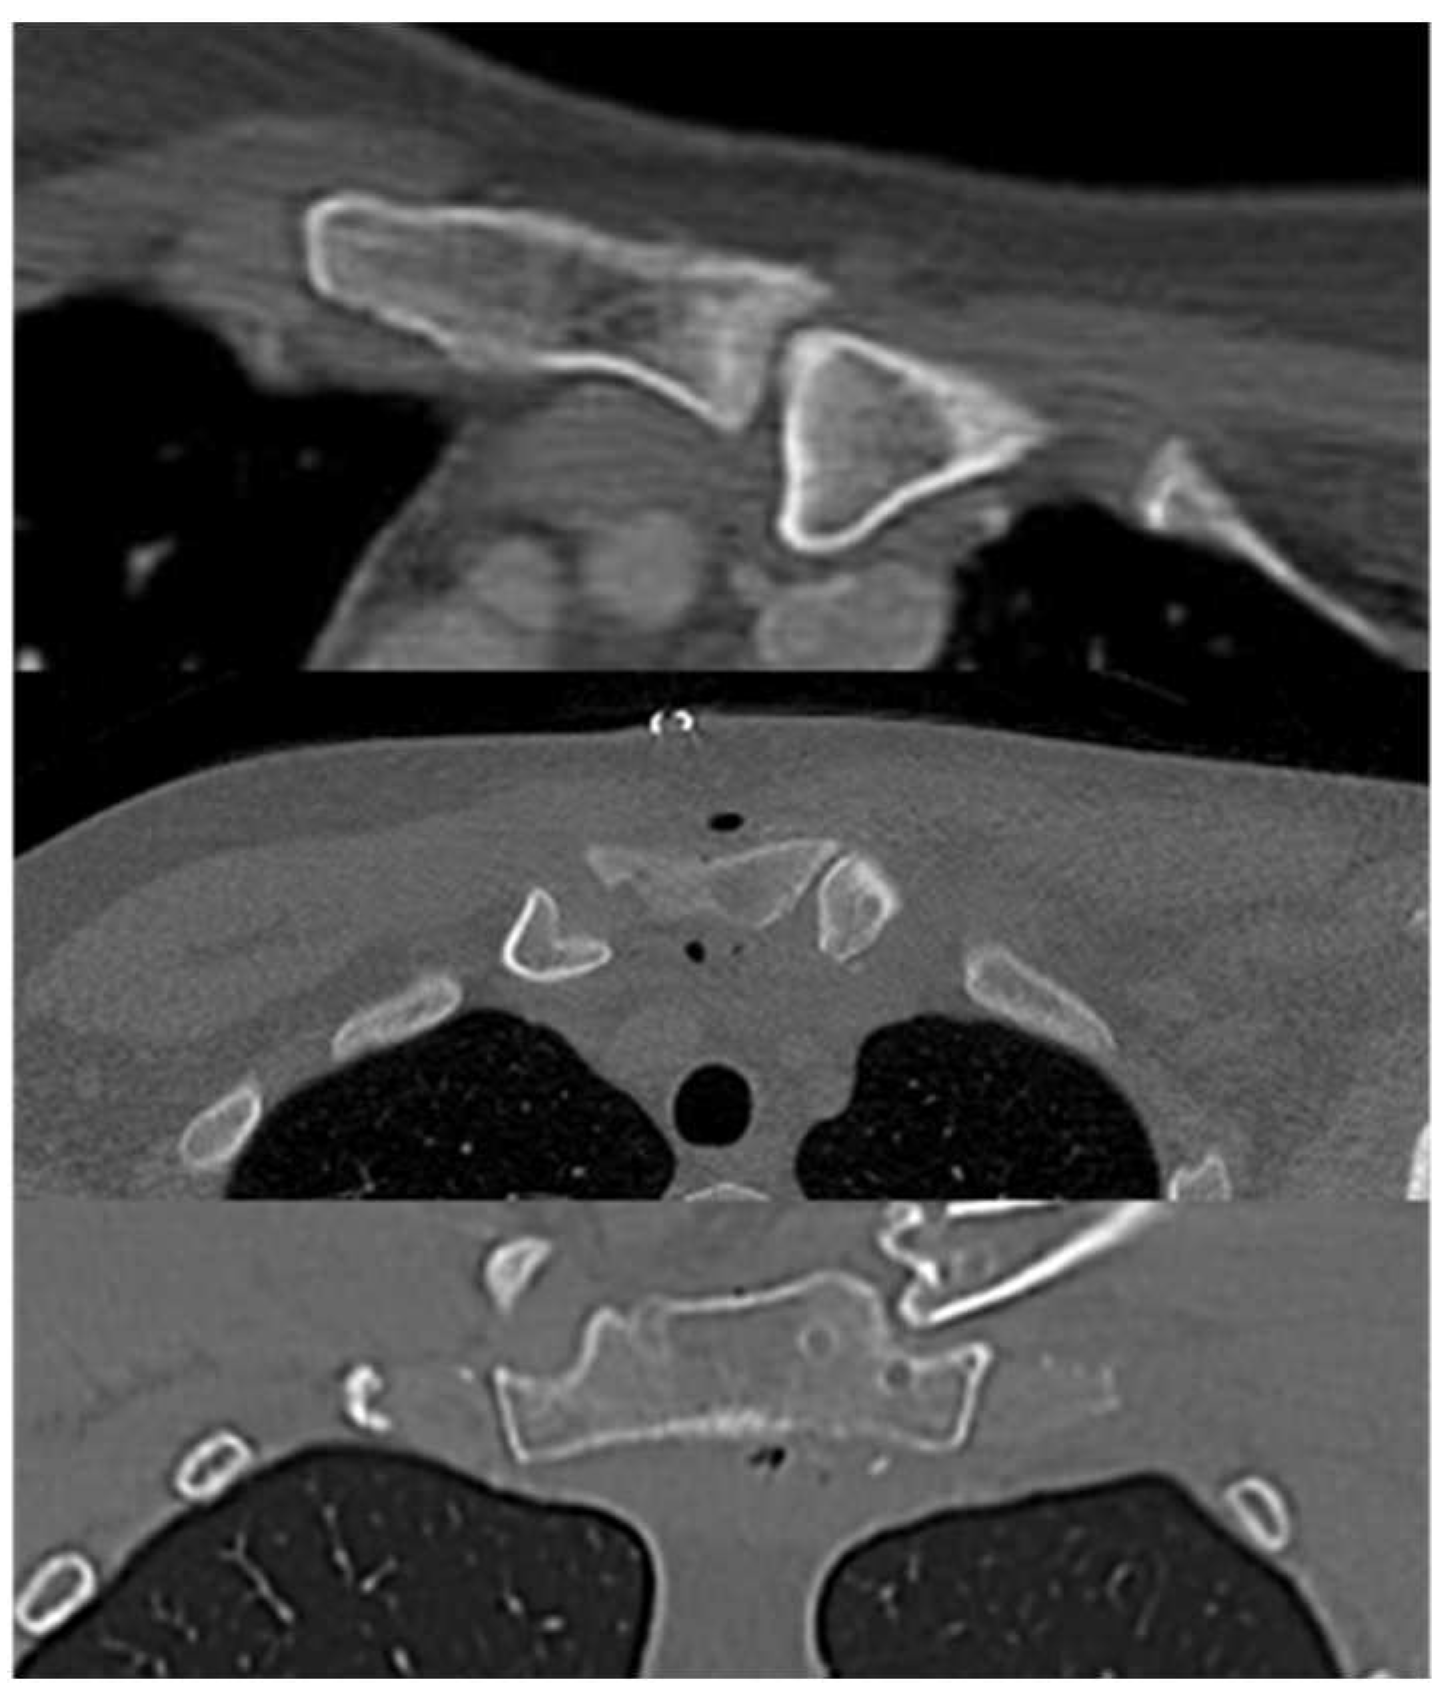

Second stage was an open reduction of the SCJ and subsequent stabilization with the autologous semitendinosus tendon graft (Figure 3). In the same supine position and in a sterile field, we proceeded to exposing the SCJ, the sternal manubrium and the medial clavicle through an antero-superior straight incision extended from the middle part of the clavicle to the mid superior aspect of sternal manubrium, finding a posterior dislocation of the SCJ. After releasing the medial part of the clavicle and the articular facet of the sternum, four bone tunnels (diameter 5 mm) were arranged, two in the clavicle and two in the sternum, adequately protecting the noble structures underlying. After the reduction of the clavicle, we stabilized the joint with a figure-of-eight semitendinosus tendon graft reconstruction and then reinforced it with high strength suture tape (Figure 4). A suction drainage was also positioned after appropriate hemostasis and wash. As per post operative protocol an arm sling was recommended. Elbow, wrist and hand mobilization were allowed from day 1; at 3 weeks the patient started the rehabilitation of the shoulder. At 2 months, a new CT scan was performed and it showed a complete reduction, both on the axial and the coronal view (Figure 5 and Figure 6).

Figure 6. Pre and postoperative CT scan, 2nd patient: reduction confirmed on axial and coronal scan.